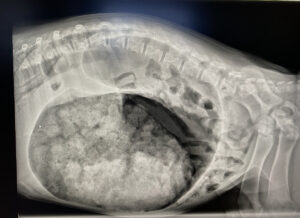

They examined the difference between two groups that were operated on for gastric dilatation-volvulus directly after a standardized stabilization protocol lasting 90 minutes, versus a group that was operated on the morning after presentation, still with the same stabilization protocol. As we all know, gastric dilatation-volvulus patients tend to present in the evening and at night.

The results were highly surprising for those of us who have believed that gastric dilatation-volvulus is a peracute event where surgery must take place very shortly after presentation.

89 dogs were operated on immediately, while 73 were stabilized pending surgery the next morning. One group was operated on 2.1 hours (median value) after presentation, the other 9.8 hours (median value) after. One dog had to wait a full 13.7 hours, without this negatively affecting the outcome.

There was no difference in survival between the two groups either at discharge or one month after the procedure. Although the degree of ventricular rotation was distributed somewhat differently between the groups, the degree of gastric wall necrosis was similar and low across both groups. High lactate values 24 hours after initiated fluid therapy were found to be a negative prognostic marker for survival, both during postoperative hospitalization and up to 1 month after the procedure.